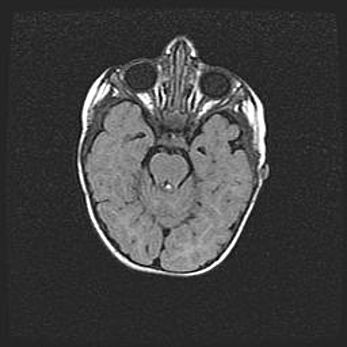

Наружная гидроцефалия с возможной атрофией височных областей.

Возраст: 28 дней

Вес: 3670 г

Пол: мужской

Окружность головы: 38 см

Срок гестации: 40 недель

Гидроцефалия головного мозга у новорожденных – это заболевание, которое характеризуется скоплением избыточного количества спинномозговой жидкости в желудочковой системе головного мозга в результате затруднения её перемещения от места выработки к месту поглощения в кровеносную систему или вследствие нарушения абсорбции. При открытой наружной форме гидроцефалии у новорожденных расширяются и переполняются субарахноидные пространства.

При нормотензивных  формах,  которые,  как  правило,  являются  следствием  перенесенных ишемических  повреждений  паренхимы  мозга,  возможно  сочетание микроцефалии  с нормотензивной гидроцефалией. В основе данных изменений лежит атрофия больших полушарий с преимущественной  локализацией  в  лобно-височных  областях.